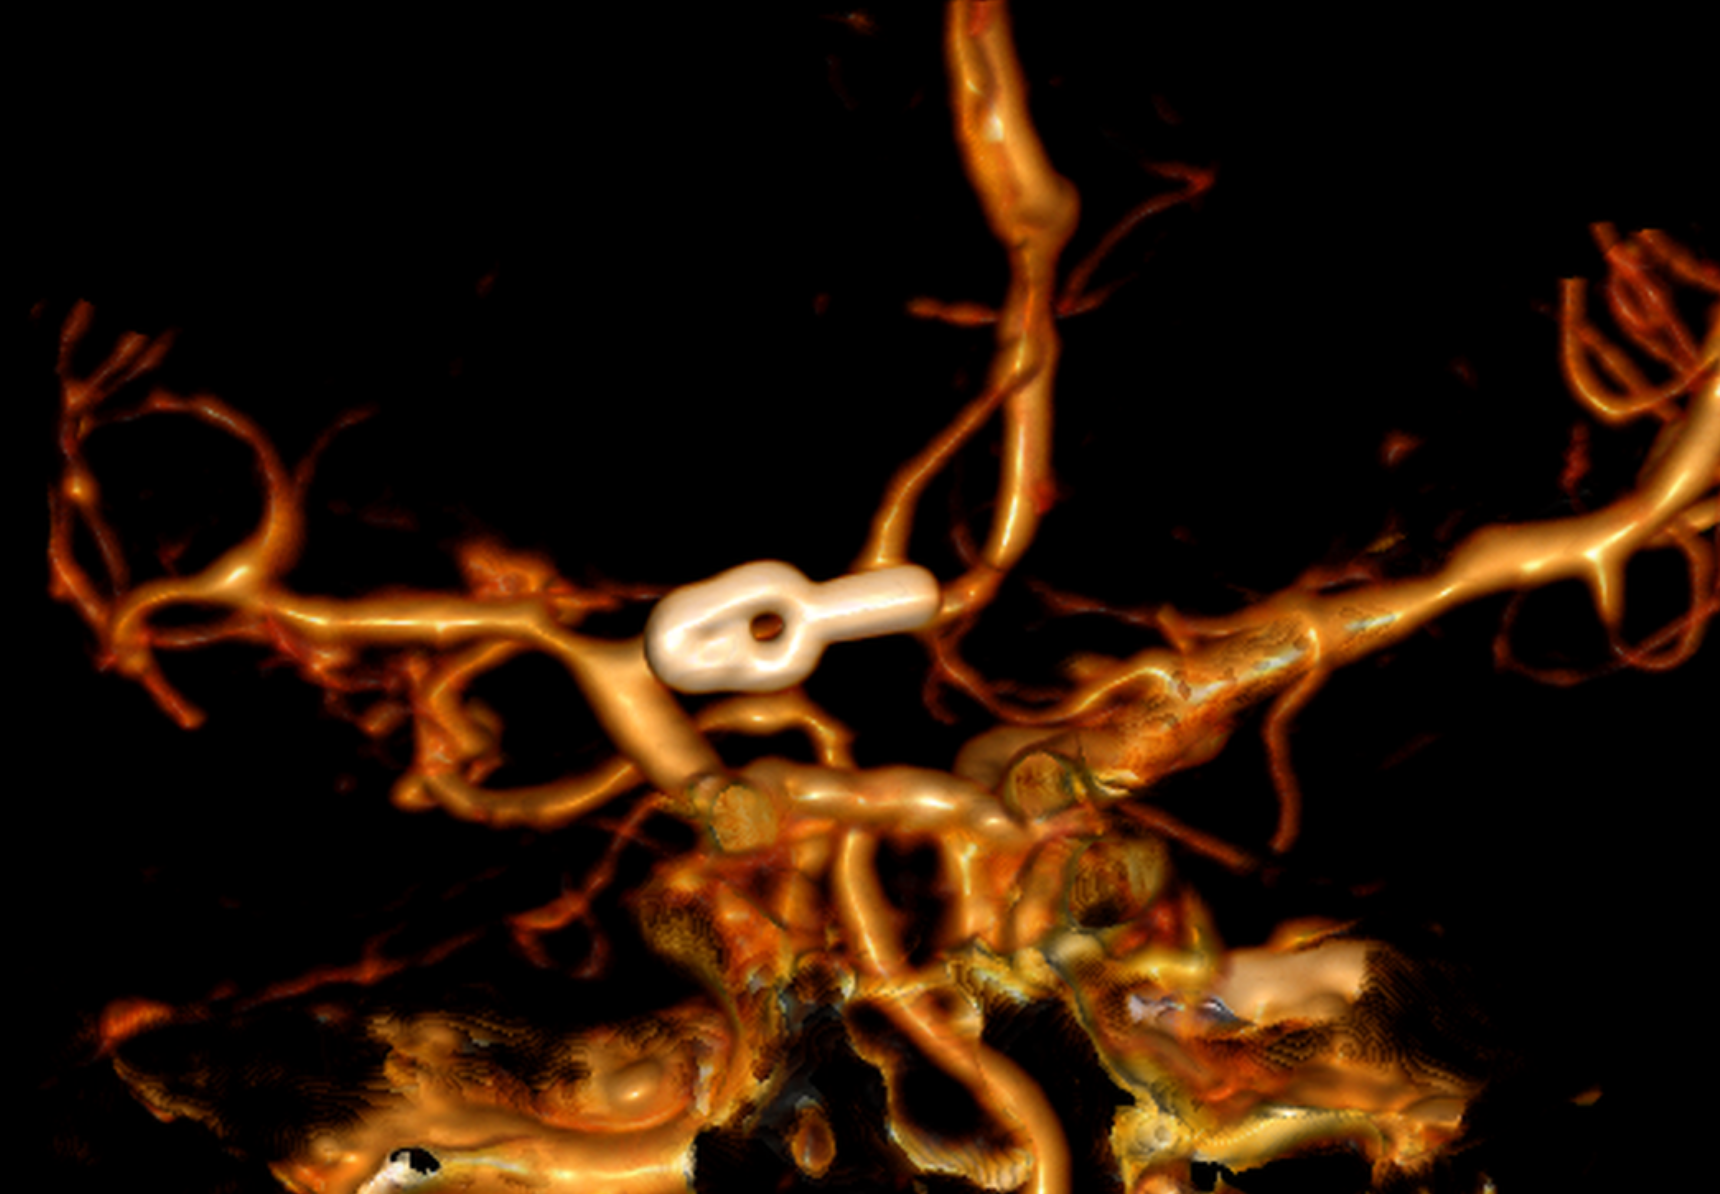

The typical bleeding pattern is seen after aneurysm rupture. The shape and location of the aneurysm can predict its behavior and also determine which treatment is preferred. Alternatively, if the aneurysm has a low risk of rupture or a high surgical risk, we may choose to surveil it with serial imaging. The intervention is designed to block the blood flow into the aneurysm, therefore eliminating the risk of hemorrhage. It can be performed endovascularly – by filling the aneurysm from within (“endovascular coiling”), or by open microsurgical techniques (“clipping”).

Surgical clipping (resolution)

A small incision is made behind the hairline and a piece of bone is removed to allow access to the aneurysm. The aneurysm is identified under microsurgical vision, with its branches and one or more clips applied externally to its neck. When the aneurysm is healed, the bone is replaced with special titanium plates and the incision is closed.

Clipped aneurysm

Aneurysm clip and support

Recurrent aneurysm seen near clips

3D brain angiography showing an aneurysm